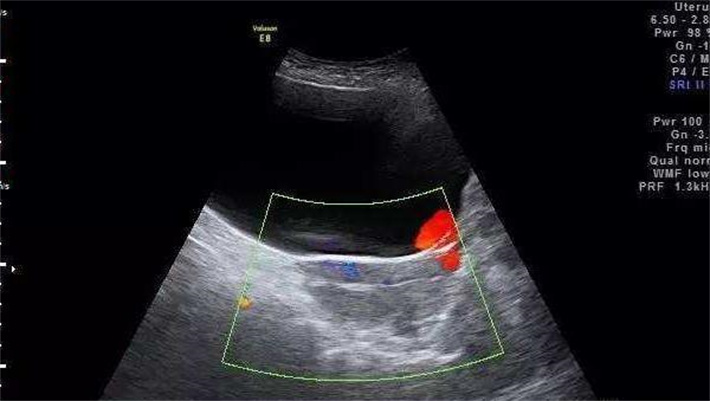

在决定赴美做试管前,一次全面且细致的身体检查是必不可少的。超声检查能清晰地展示囊肿的位置、大小、形态以及内部结构,帮助医生初步判断囊肿的性质。经阴道超声检查,能近距离观察卵巢和囊肿的细节,分辨率高,对于较小的囊肿也能精准识别。除了超声,女性还需进行一系列的激素水平检测,包括卵泡刺激素(FSH)、黄体生成素(LH)、雌二醇(E2)、孕酮(P)、睾酮(T)和催乳素(PRL)等。这些激素的水平变化反映着卵巢功能和内分泌状态。FSH和LH水平异常,可能提示卵巢储备功能下降;E2水平不稳定,会影响子宫内膜的生长,进而影响胚胎着床。

在促排卵期间,定期的超声检查能够清晰地捕捉到囊肿的大小变化、位置移动以及卵泡的生长动态。专家会根据超声检查的结果,及时调整促排卵药物的剂量和使用时间。如果发现囊肿在短时间内迅速增大,专家会暂停用药,并对囊肿进行进一步评估,必要时采取手术等干预措施,以避免囊肿破裂或扭转等危险情况的发生。

在取卵手术前,专家会通过超声再次确认囊肿的位置,在取卵过程中,借助先进的超声引导技术,精准地避开囊肿,减少对囊肿的刺激,降低囊肿破裂的风险。